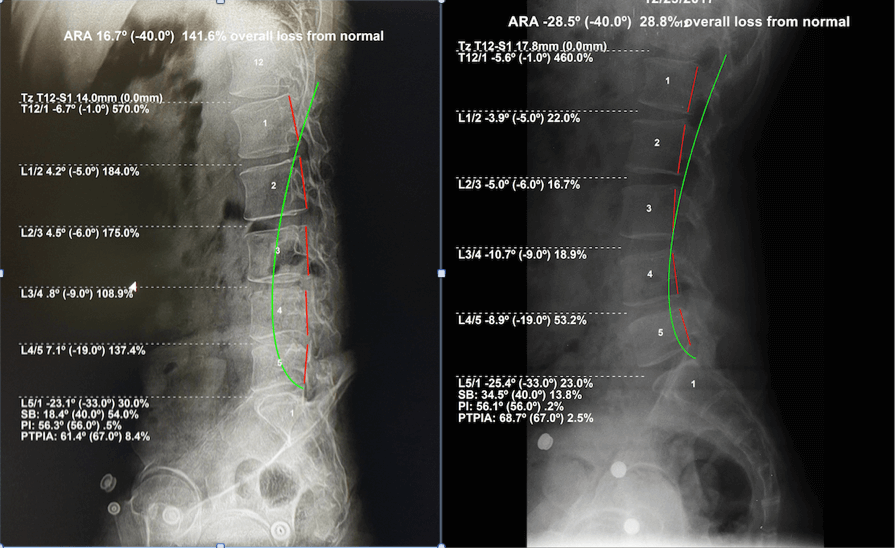

Digital posture analysis and digital x-rays for tracking progress